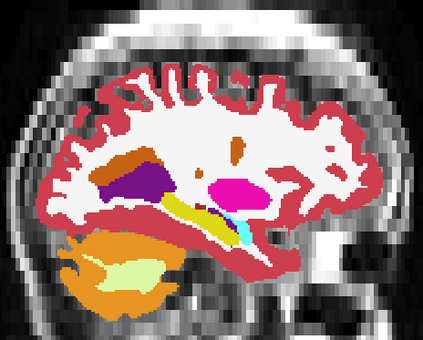

Brain atrophy and white matter hyperintensity (WMH) are critical neuroimaging features for ascertaining brain injury in cerebrovascular disease and multiple sclerosis. Automated segmentation and quantification is desirable but existing methods require high-resolution MRI with good signal-to-noise ratio (SNR). This precludes application to clinical and low-field portable MRI (pMRI) scans, thus hampering large-scale tracking of atrophy and WMH progression, especially in underserved areas where pMRI has huge potential. Here we present a method that segments white matter hyperintensity and 36 brain regions from scans of any resolution and contrast (including pMRI) without retraining. We show results on six public datasets and on a private dataset with paired high- and low-field scans (3T and 64mT), where we attain strong correlation between the WMH ($\rho$=.85) and hippocampal volumes (r=.89) estimated at both fields. Our method is publicly available as part of FreeSurfer, at: http://surfer.nmr.mgh.harvard.edu/fswiki/WMH-SynthSeg.